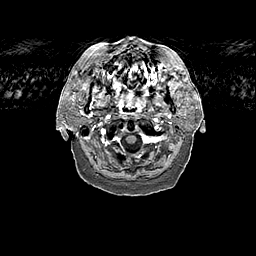

Glioma overlay -- Slice #3

[Home][Help][Clinical] Slice 3